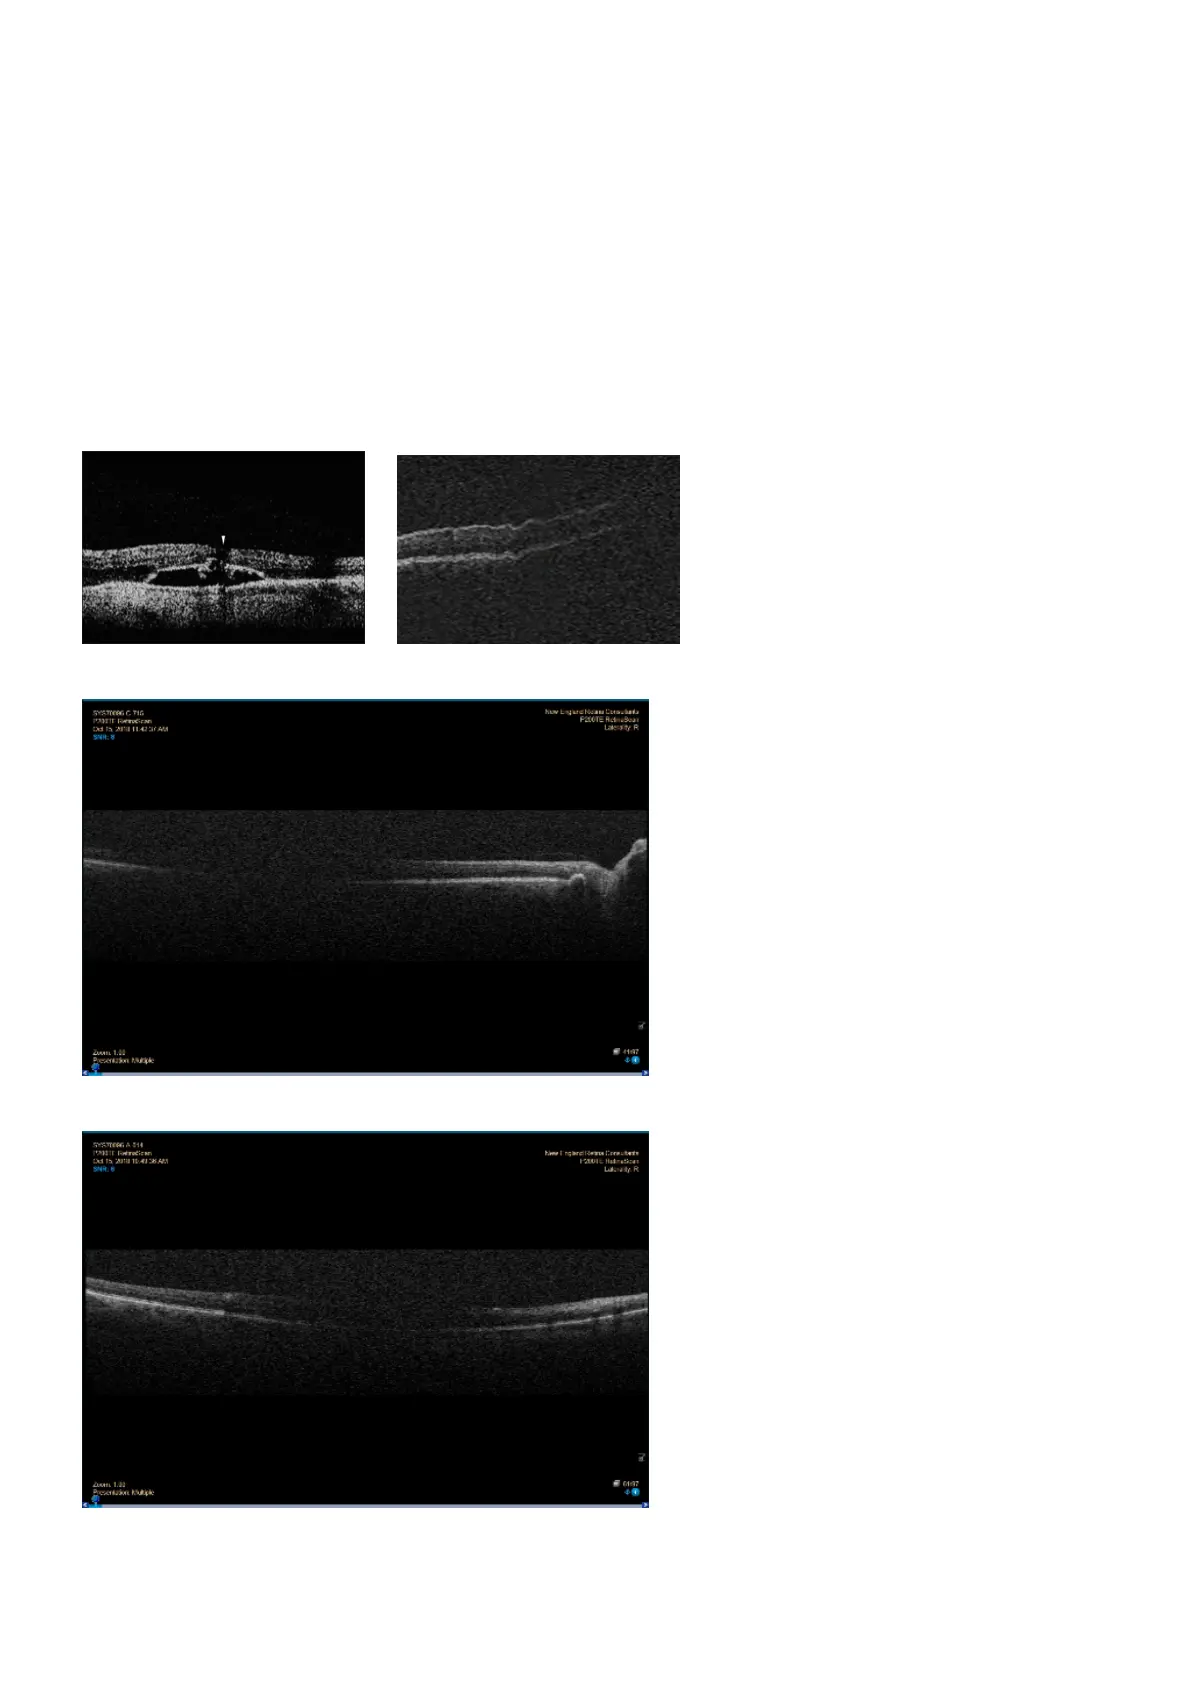

If a local weak signal covers essential parts of the image, for example the fovea, the operator should

document the image as non-evaluable. If a local weak signal does not cover essential parts of the image

the operator should document the image as evaluable.

FIGURE 14: Examples of local weak signal strength.

FIGURE 15: Example of local weak signal near the fovea.

FIGURE 16: Example of local weak signal with acceptable global SNR.